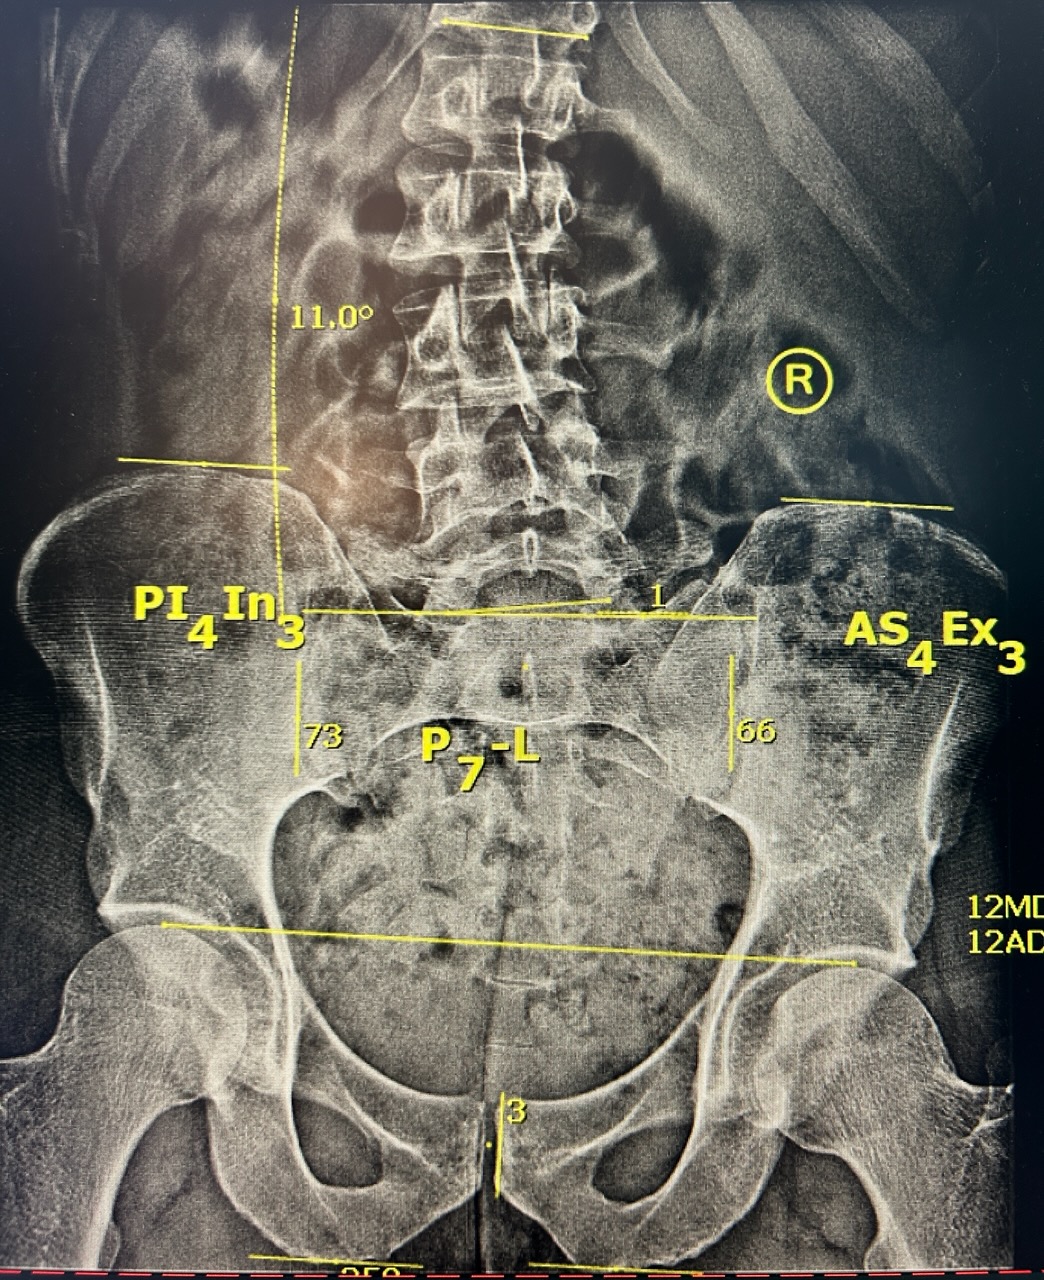

We don’t chase symptoms we uncover the real reason behind your pain. Using tools like upper cervical chiropractic, motion-sensing diagnostics, and functional nutrition resources, we treat the problem at its source for real and lasting relief.

Everybody requires unique care. We combine traditional care with modern technologies, like percussive massagers, disc decompression tables, and detailed imaging, to create custom plans for you.